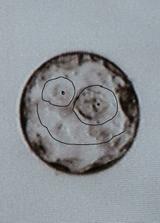

Duben 2010.. 8. pokus - ET 2 embrya - PK, expandující blastocysty. Transfer byl v den, kdy jsme oslavili 5 let, co mě manžel požádal o ruku. Opět se to v car povedlo, teď to jen nezakříknout.. 23. den po ET jsem krvácela, ale

25. května (29. den po ET) jsme na UTZ viděli srdíčko. 54 kg (v lednu 51kg, v dubnu 53kg)